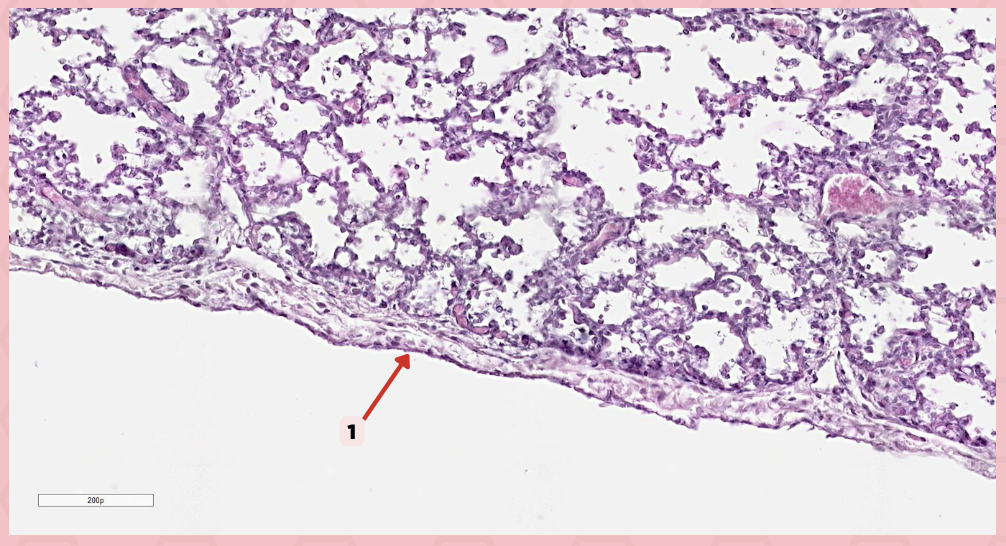

Simple squamous epithelium (Mesothelium)

The surface related to the pleural cavity is in line with what type of epithelium?

Visceral pleura

Identify the structure labeled as 1.

Visceral Pleura

What type of pleura is a thin layer of connective tissues that borders on the outside by mesothelium?

Simple Squamous Epithelium

What epithelium lines the red arrow?

Mesothelium

Identify the structure labeled as 1.